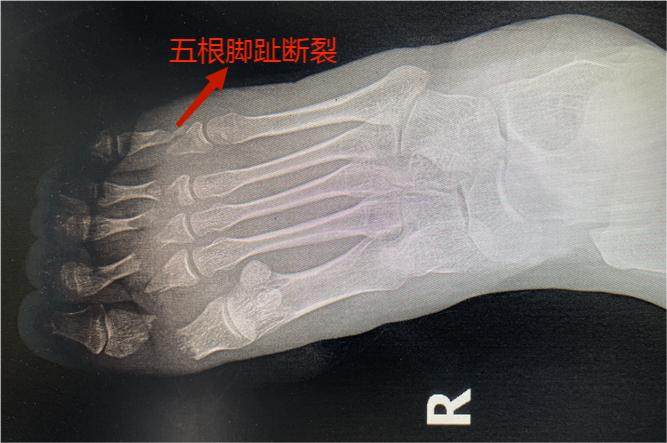

女子5根腳趾被700多公斤的重物砸斷,晉城大醫(yī)院鏖戰(zhàn)6個(gè)小時(shí)全部接回!

二十多歲的小薇,不慎被700多公斤的重物砸傷右腳,疼痛不止,同事立即將她送往晉城大醫(yī)院。醫(yī)生立即進(jìn)行查體和相關(guān)檢查發(fā)現(xiàn),即便是工作時(shí)穿了鐵鞋保護(hù),巨大的重力仍將1-5趾的趾骨砸斷,5個(gè)腳趾綿軟無(wú)力,比骨折更嚴(yán)重的是5根腳趾所有的血管全部損傷,末梢冰涼,完全沒(méi)有血液循環(huán)。